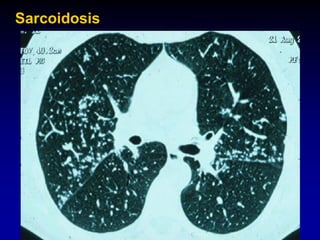

Sarcoidosis. CT scan shows nodular thickening of the bronchovascular

bundles (solid arrow) and subpleural nodules (dashed arrow), illustrating the

typical perilymphatic distribution of sarcoidosis.

Sarcoidosis. CT scanshows nodular thickening of the bronchovascular bundles (solid arrow) and subpleural nodules (dashed arrow), illustrating the typical perilymphatic distribution of sarcoidosis.